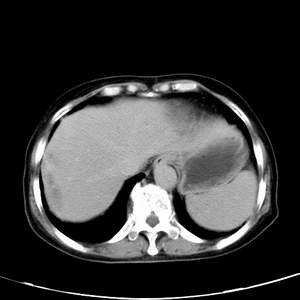

患者,女性,77岁,右上腹胀痛月余。afp正常。ca125升高。即往无肝炎病史。

肝右叶病灶是胆管细胞癌吗?门静脉右支癌栓形成?右侧肾上腺有问题吗?

快进快出符合肝癌表现

病灶渐进性向心性强化,延时病灶中心见条片状高密度影,局部见肝包膜回缩征,结合病人无肝炎病史,考虑肝右叶胆管细胞癌,门脉右支癌栓形成。